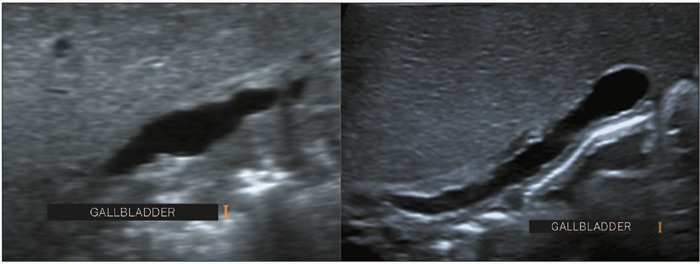

Materials and methods: This was a retrospective study of the ultrasound images of 44 patients with neonatal cholestasis. We excluded 18 patients in whom a final diagnosis of BA was not confirmed or who were lost to clinical follow-up. The main ultrasound findings evaluated were gallbladder length and morphology; triangular cord thickness; hepatic artery enlargement; hepatic subcapsular flow; cysts in the porta hepatis; presence of a distinct triangular cord with linear, tubular, or round hypoechoic portions; and polysplenia syndrome.

Results: Abnormal gallbladder morphology and triangular cord thickening were the main ultrasound findings in the patients with BA. Gallbladder abnormalities were present in all patients. Hepatic artery enlargement was the third most common finding, present in 19 (73%) patients. Six patients (23%) had subcapsular arterial flow and four (15%) had cysts in the porta hepatis. Hypoechoic or cystic portions of the triangular cord were present in three patients (11%), and we found that BA was accompanied by polysplenia syndrome in three patients (11%).